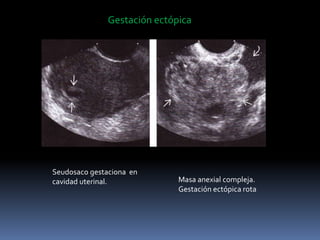

Pseudosaco en gestación ectópica

- Acumulación pequeña de liquido

cavidad endometrial, con ausencia

de saco decidual doble.

Rotura de una gestación ectópica

tubarica

Gestación ectópica

Seudosaco gestaciona en

cavidad uterinal. Masa anexial compleja.

Gestación ectópica rota

Gestación ectópica Seudosaco gestacionaen cavidad uterinal. Masa anexial compleja. Gestación ectópica rota